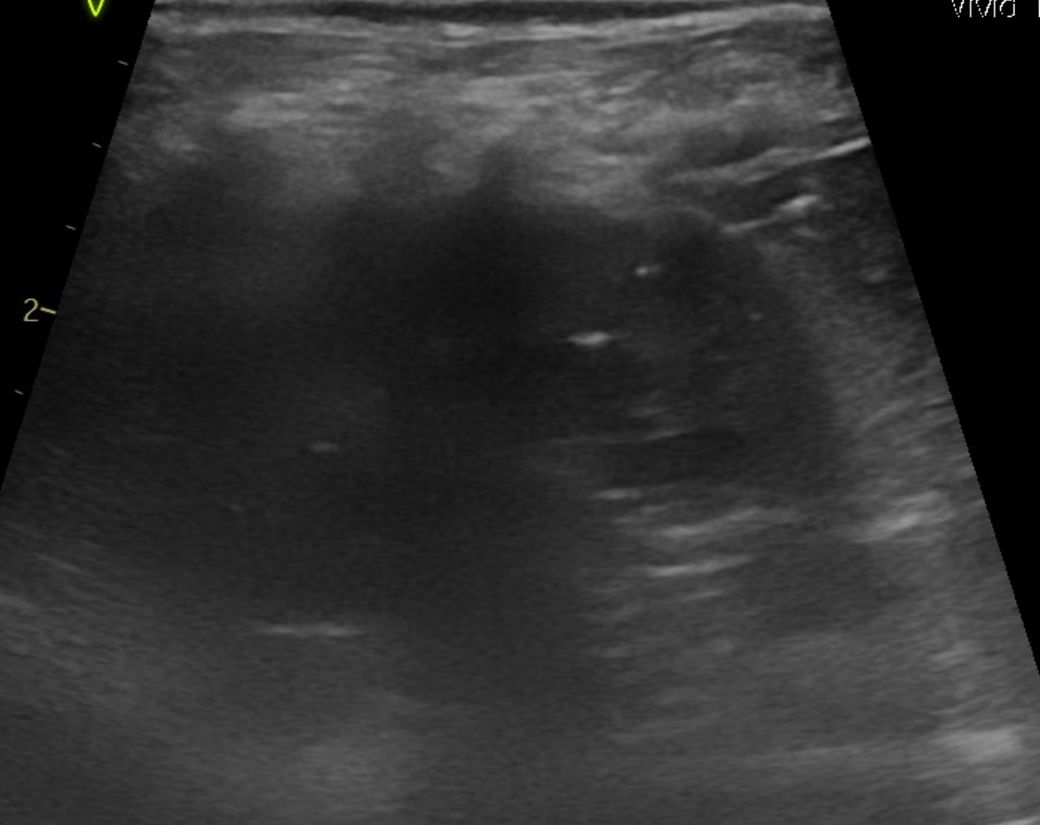

강아지 신장결석 종류 모양만으로는 판단이 안되나요? 소변에선 크리스탈이 발견된게 없다고 합니다

모양만으로 추측 조차 할수가 없는건가요? 한번 봐주시면 감사하겠습니다.

예, 없습니다. 결석이 매우 커진 상태 (몇센치미터 크기 정도)로 커졌을때나 일부 추정되지만 겉면과 내부 코어의 씨앗의 성분은 별도라 이때는 또 성분검사를 해야 하는정도로 부정확합니다.